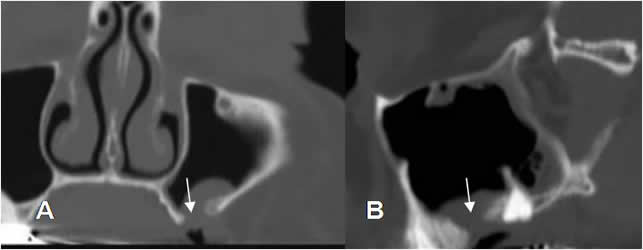

Fig 55. Sinusitis odontogénica.

A: TAC axial, B y TAC reconstrucción sagital. Engrosamiento en la mucosa del seno maxilar, por sinusopatía. Las raíces de los molares y premolares han roto el piso del seno, debiendo considerar etiología odontogénica.

Fig 55 A. Fístula.

A: TAC reconstrucción coronal y B: TAC reconstrucción sagital. Engrosamiento en la mucosa del seno maxilar, con defecto óseo del piso y comunicación con la cavidad oral, por la formación de fístula.